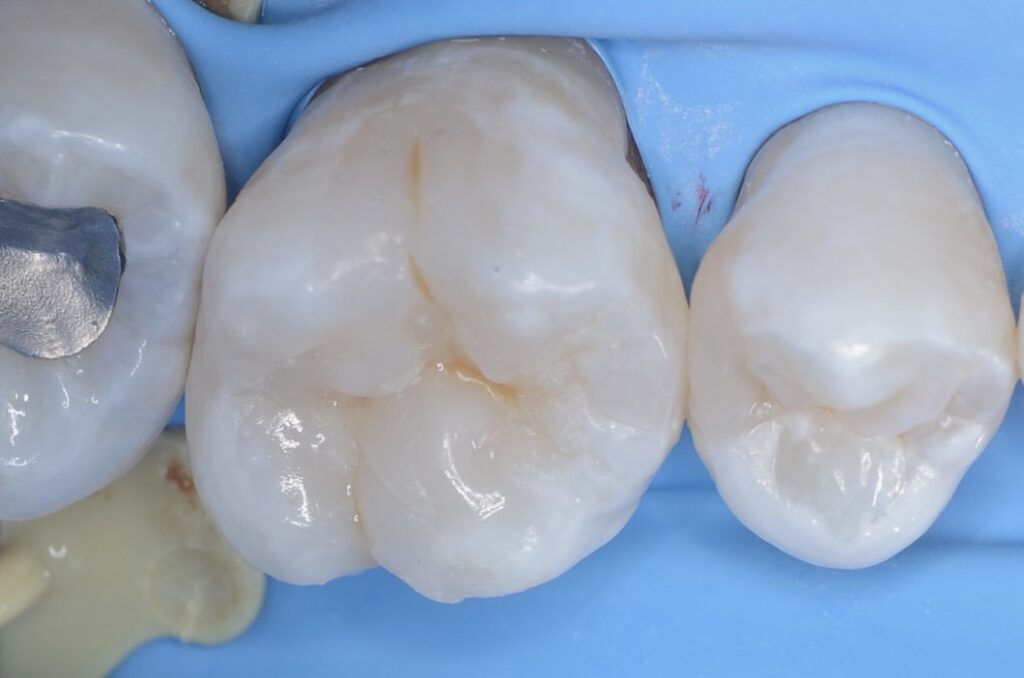

40代 虫歯治療 ダイレクトボンディング #51

Before

After

| 年齢 | 40代 | 治療方法 | ダイレクトボンディング |

|---|---|---|---|

| 性別 | 男性 | 通院回数 | 3回 |

| 主訴 | できるだけ歯を削る量を少なくしてむし歯を治したい | 費用 | 115,500円(税込) |

| 治療のメリット | 歯を削る量を少なくできる・自然な見た目・境目がピッタリできる | ||

| 治療のデメリット | 大きい虫歯治療には適応できない場合がある | ||